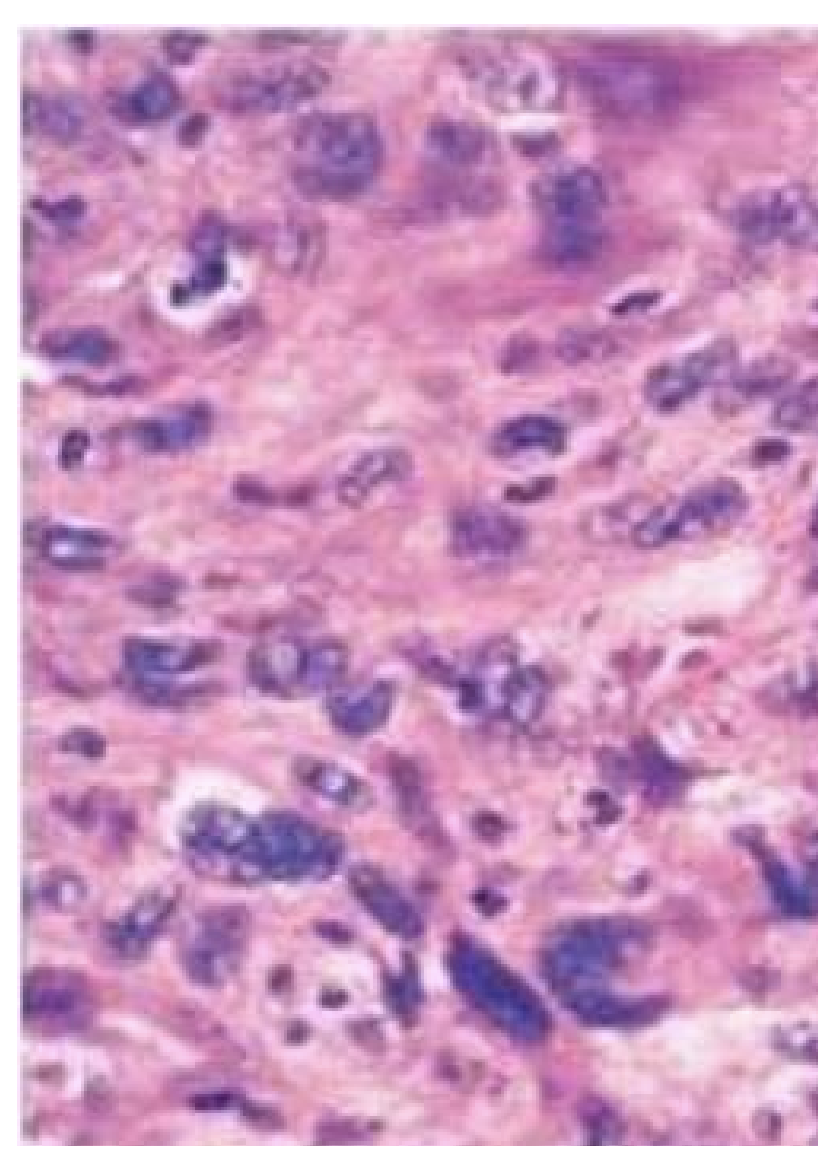

Dette præparat stammer fra en 25 årig mand. Hvilken histologisk diagnose svarer bedst til billedet?

a. Planocellulært karcinom

b. Germinalcelletumor

c. Malignt melanom

d. Lipom

*b. Germinalcelletumor